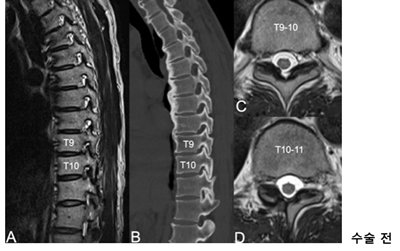

<»çÁø  ³»½Ã°æ ÈÄ¿ÜÃø Ãß°£°ø È®Àå¼ú »ç·Ê> °ú°Å °æÃß ÈıüºÇü¼ú°ú °³¹æÇü ÈäÃß µð½ºÅ©ÀýÁ¦¼úÀ» ¹ÞÀº ȯÀÚ, ÈäÃß 9~10¹ø°ú 10~11¹ø ºÎÀ§¿¡ Ãß°£°ø ÇùÂøÁõÀÌ ¹ß°ßµÅ ³»½Ã°æ ÈÄ¿ÜÃø Ãß°£°ø È®Àå¼ú·Î È£ÀüµÊ.